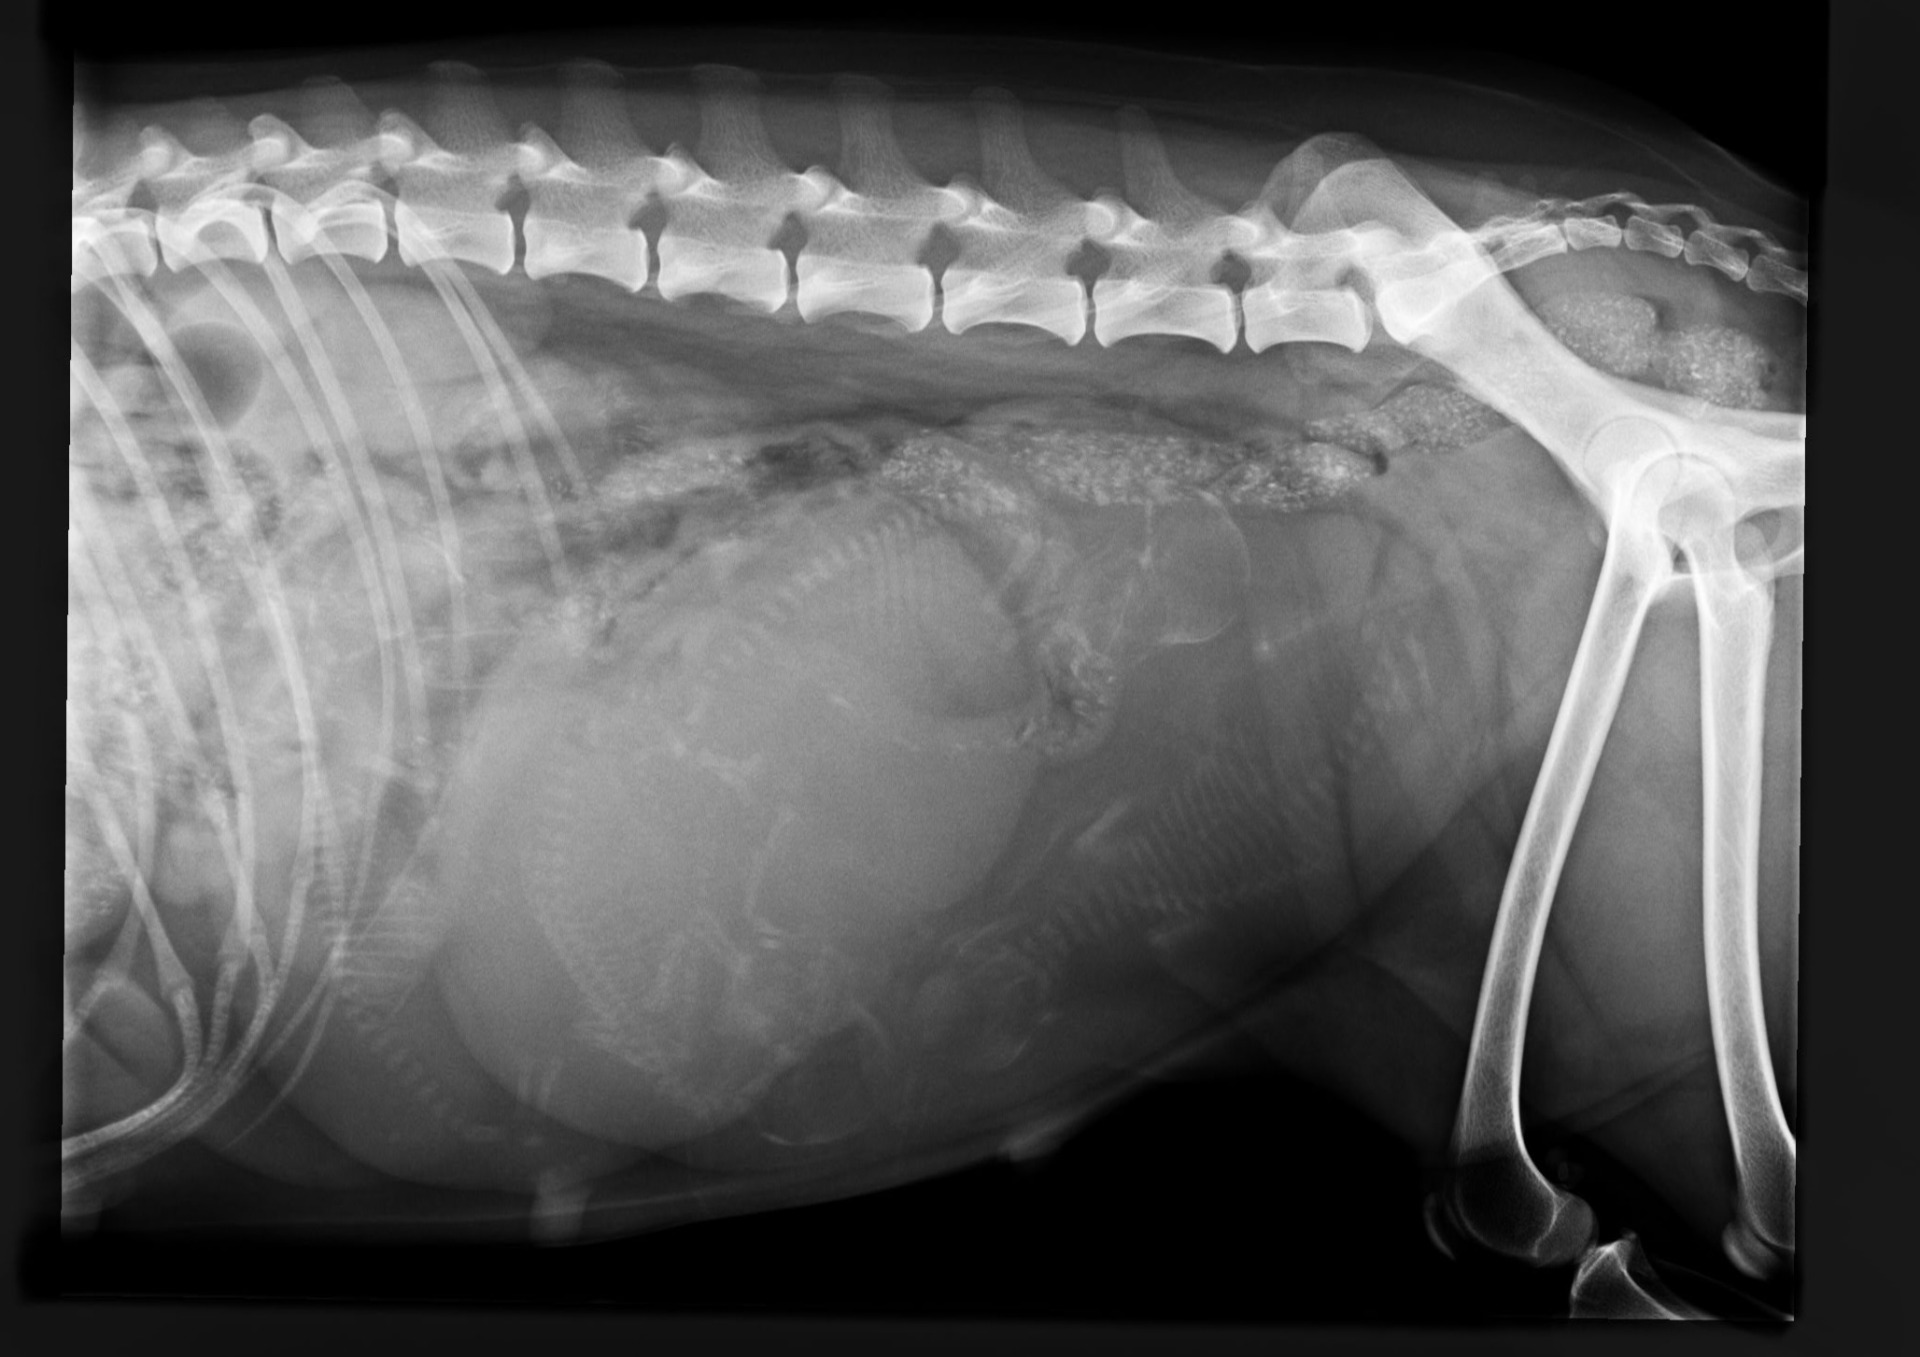

Lola on käynyt tiineysröntgenissä ja 4 pientä sielä näkyi❤️ Nyt jäädään odottelemaan, koska alkaisi tapahtua🤭🤭